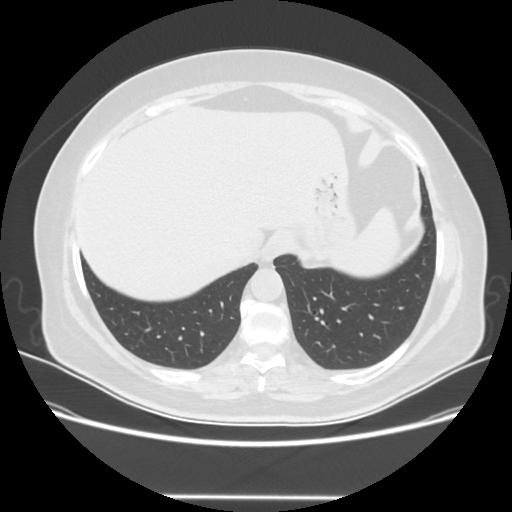

Reconstructed NATIVE CT scan (cycle consistency)

Full window (WL 1023.5, WW 4095 β†’ Low βˆ’1024, High +3071)

Actual HU range: [-1024.0, 993.2]

Lung window (WL -600, WW 1500 β†’ Low βˆ’1350, High +150)

Actual HU range: [-1350.0, 150.0]